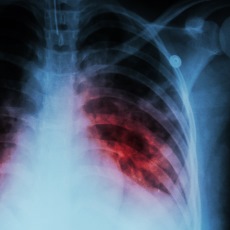

- Tests for TB disease in the lungs usually include testing samples of your sputum and having chest x-rays.

Tuberculosis (TB) is a bacterial disease that usually attacks the lungs. But it can also attack other parts of the body, including the kidneys, spine, and brain.